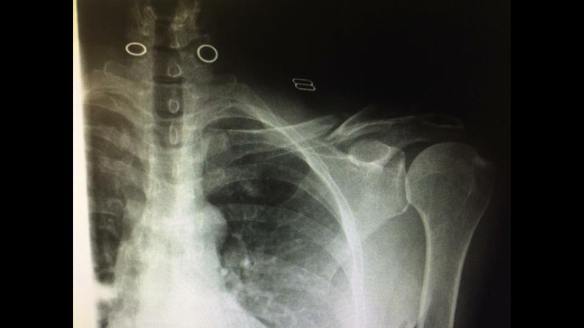

We both declined emergency services. Our injuries were fairly common for any cyclist that comes to grief against the tarmac. We both had road rash on our left side and significant soreness. I had severe whiplash from my head bouncing off the tarmac. While our road rash was common we had both experienced concussions. Lori took it to the next level by having road rash not only on her left side but with road rash on the right side of her face. Additionally, at some point she was lucid enough to perform a very astute and accurate self-diagnosis of a broken left clavicle. As the emergency vehicles drove away Tony loaded up our tandem in his vehicle and took Lori 1.5 miles to Checkpoint #1. I was ferried to Checkpoint #1 by Ed in his toaster.